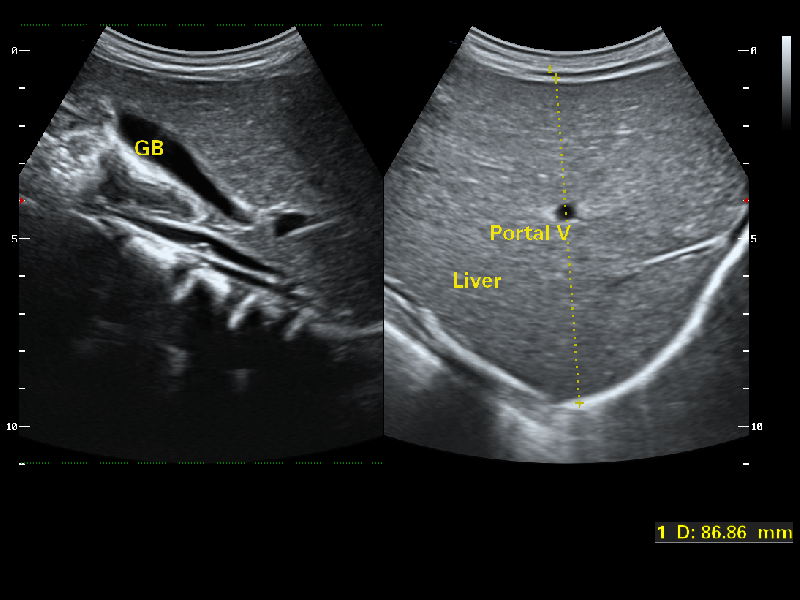

Spatial Compound Imaging utilizes several lines of sight for optimal contrast resolution, speckle reduction and border detection, with which CD40 is ideal for superficial and abdominal imaging with better clarity and improved continuity of structures.

1Mhz Low Frequency Convex transducer greatly improve the Piezoelectric crystal signal ratio, Acquire stunning Quality Images & New Generation μ-Scan + Provide High sensitivity & High Resolution for the Both near and far field, 200 degree Transvaginal Probe provides extraordinary image quality for gynaecology, Early Obstetrics scan, HD Linear Transducer achieve a Uniform image Quality, high sensitive acoustic spectrum in vascular, brest, MSK, Thyriod, Lower and upper limp, Etc and Aeroscan CD40 enhancing boundary improved visualization in 2D and Color Doppler in Echocardiogram with all premium Features loaded., CD40 Supports Ultras-wide Frequency bandwith Probes - Intra-operative, Paediatric, Neonatal, TEE, Transrectal, Volume Transducer & More.,